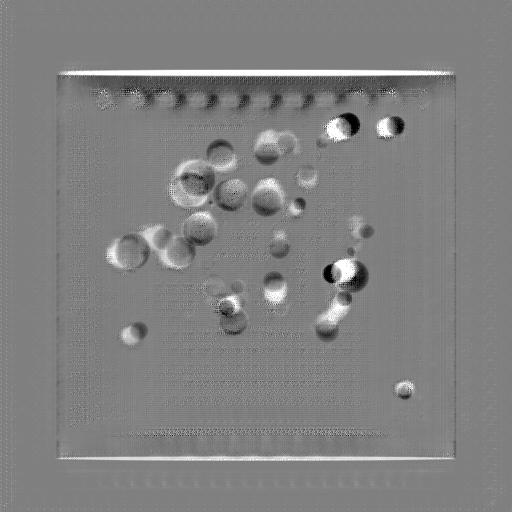

Refer to caption

Figure 13: Three examples of synthetic perspective projection images for training, intensity window: [0, 4]. The appearance (e.g., image contrast and metal image resolution) of such DRR training images is different from that of real projection images in Fig. 14.